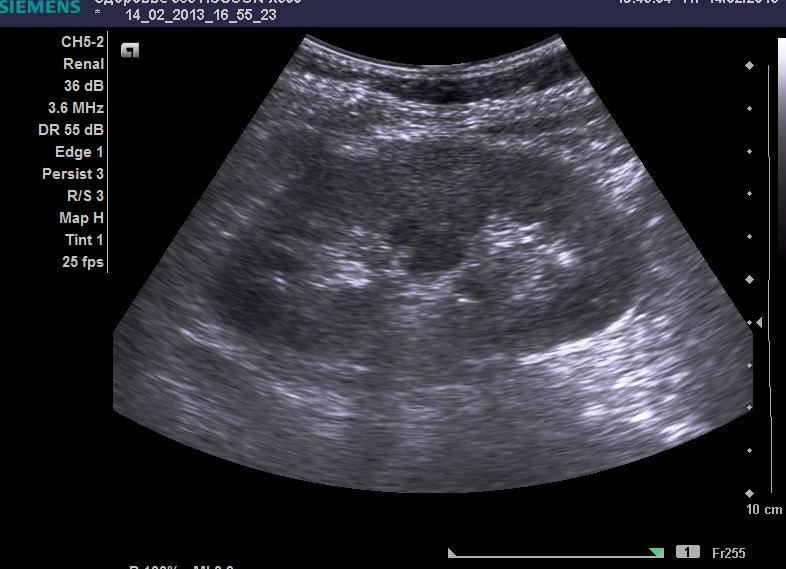

УЗИ является неинвазивной процедурой обследования организма человека, которая основана на использовании ультразвуковых волн. С помощью УЗИ можно детально рассмотреть форму органа, структурные особенности, размеры, расположение, а также двигательную активность. Также УЗИ почек и надпочечников показывает наличие или отсутствие патологии и заболевания со стороны этих органов.

Почки и надпочечники находятся в забрюшинном пространстве и хорошо доступны для ультразвукового исследования